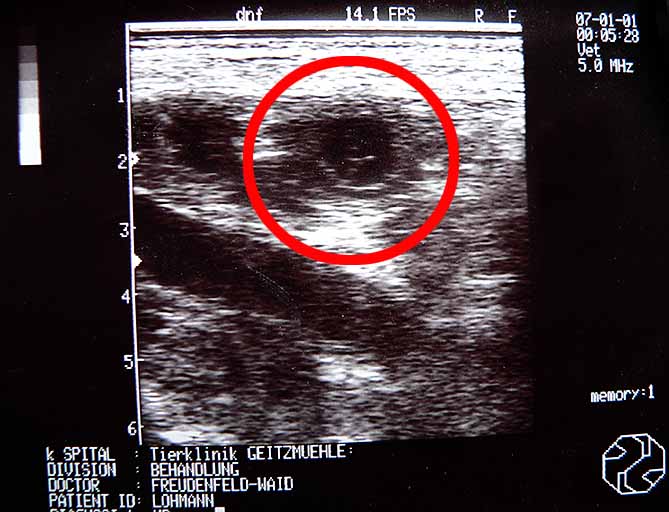

Der Ultraschall hat gezeigt, das Quendy tatsächlich tragend ist...sechs kleine schwarz-weiße ( in diesem Fall nicht weiß-schwarz ;-)) )Babys hat das Schallbild schon gezeigt.

...und das Bild vom Ergebnis des Gerangels.